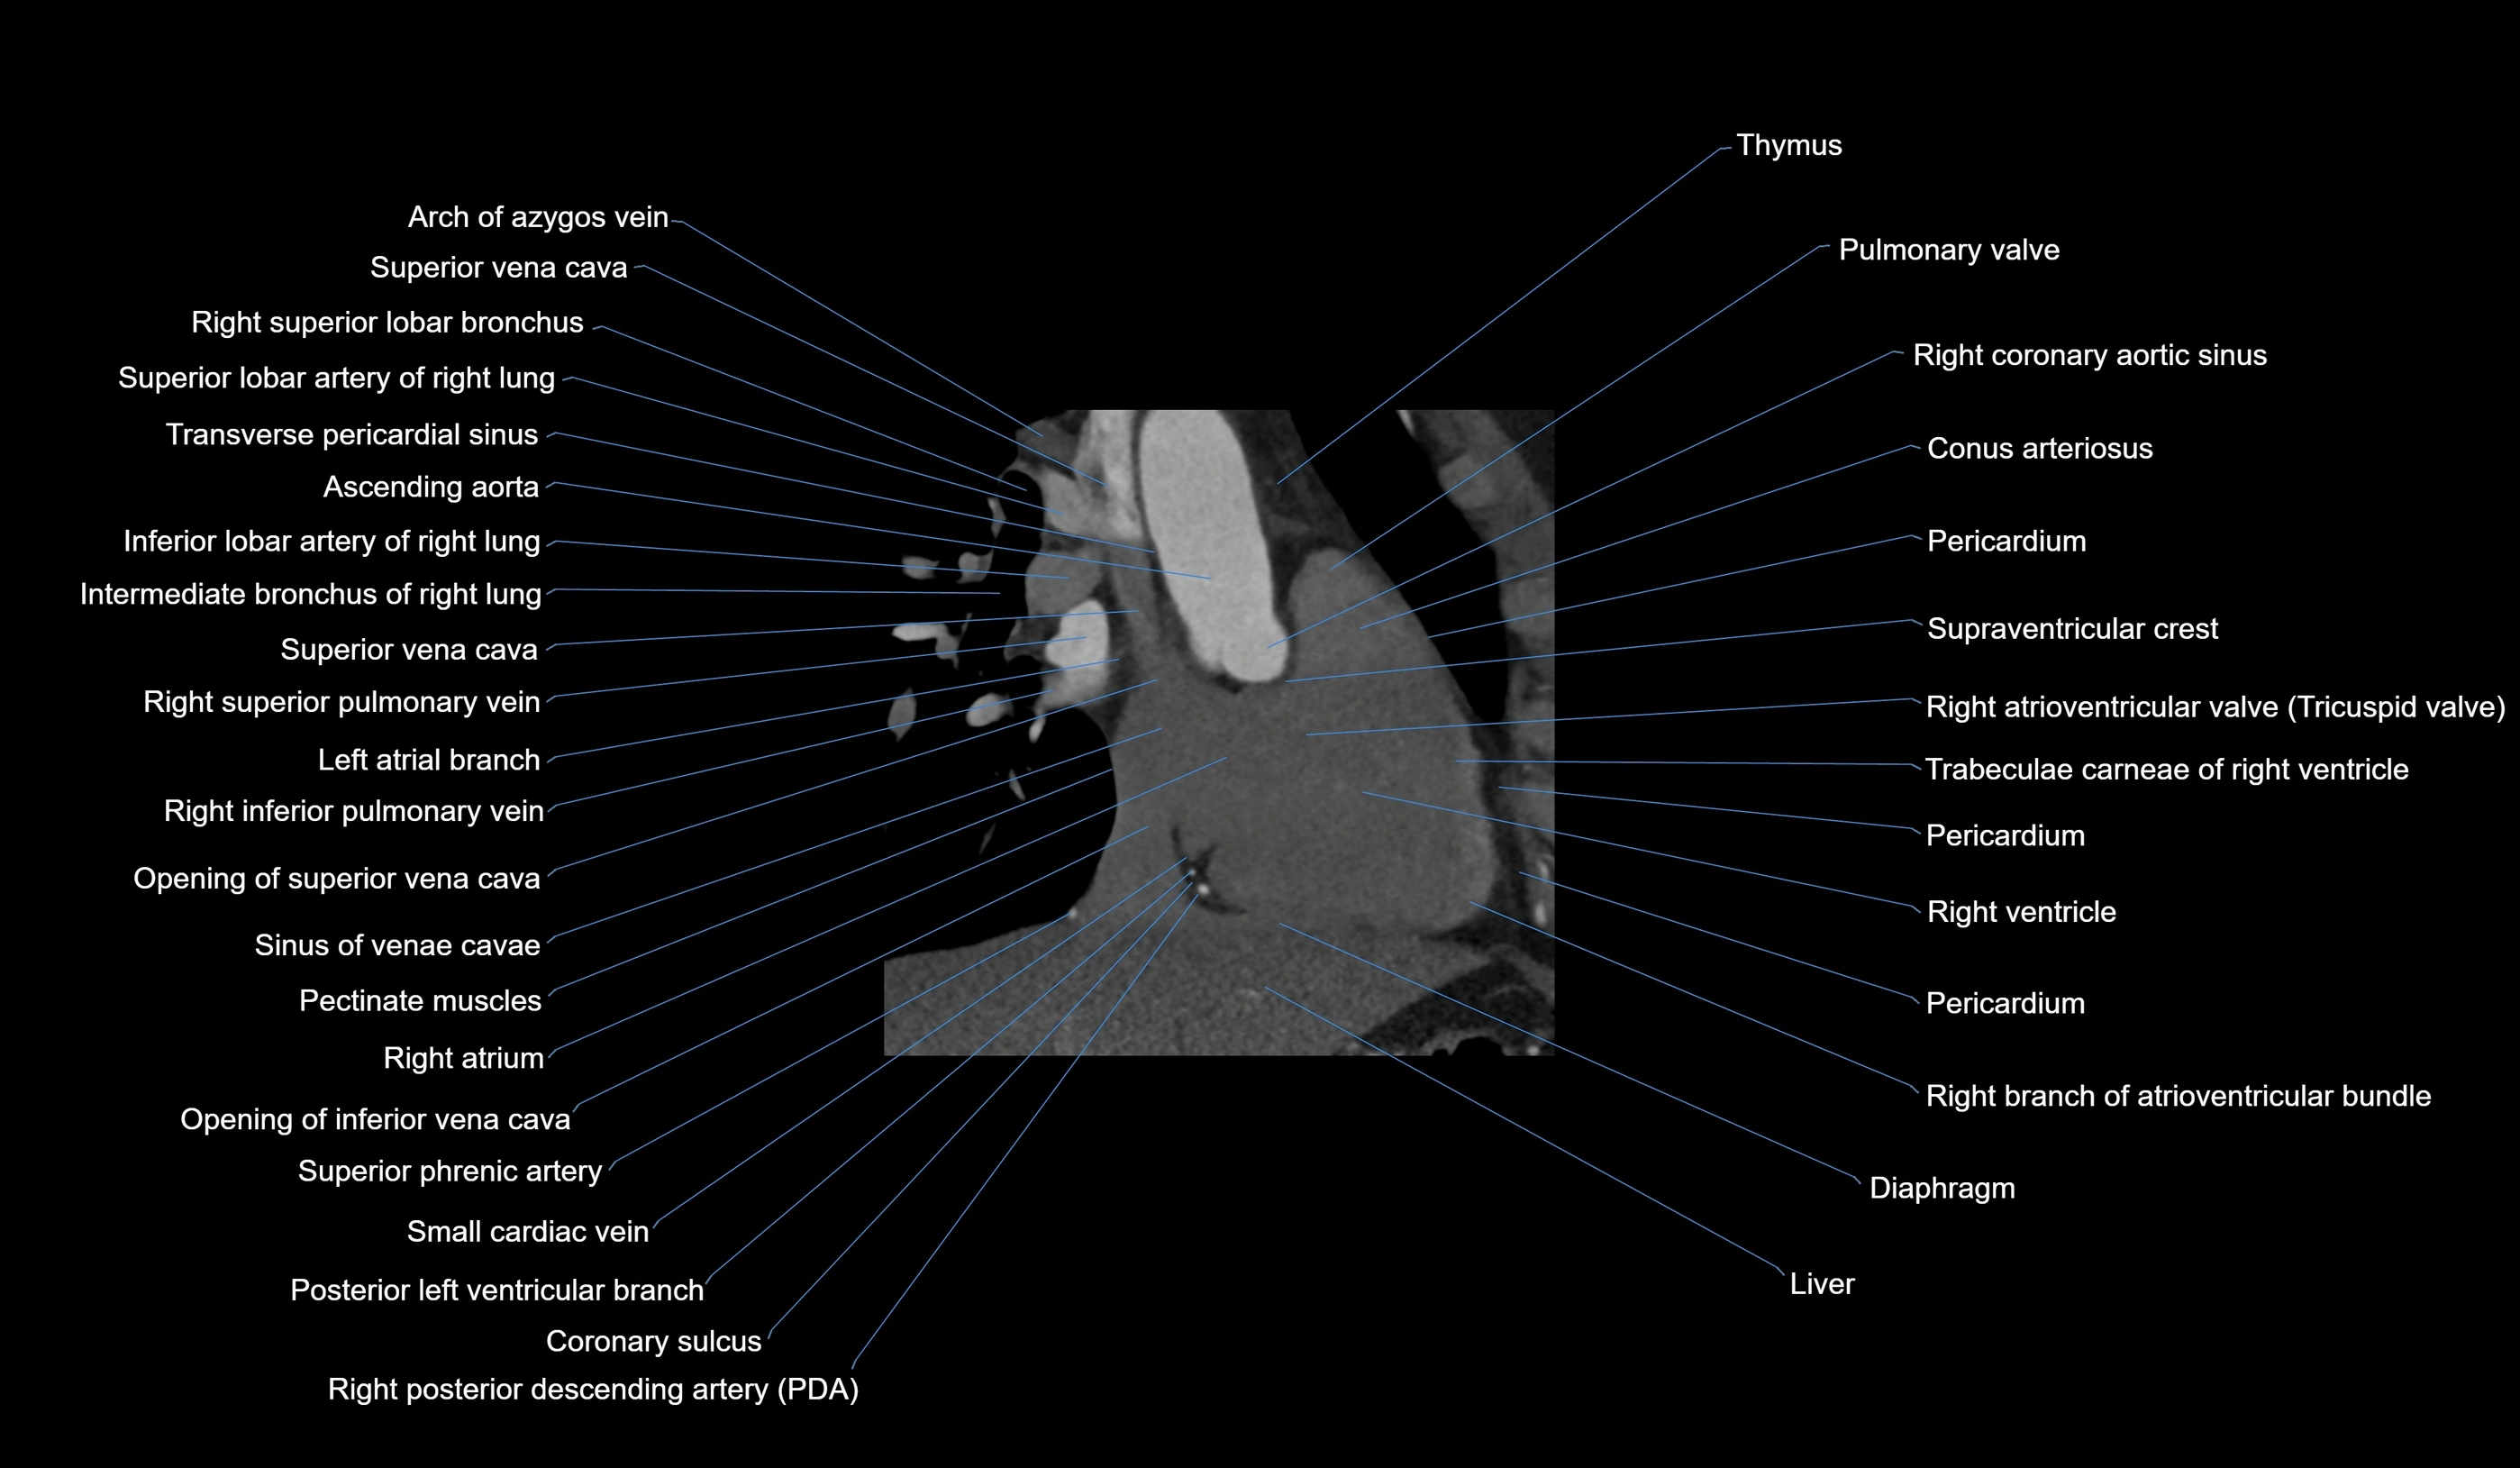

CT images